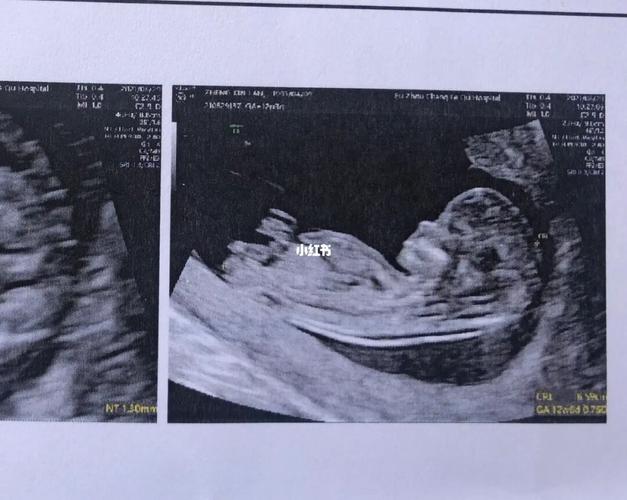

男女nt图对比,女宝nt图片

nt归来,有会看男女的亲吗?

nt过了,能看男女吗

nt nub点看男女_nt检查_女宝_母婴_孕产经验

附一张nt数据有会看男女的嘛头胎男女

NT图看男女

nt看男女

NT图如何看男女

nt照平躺的是女孩图